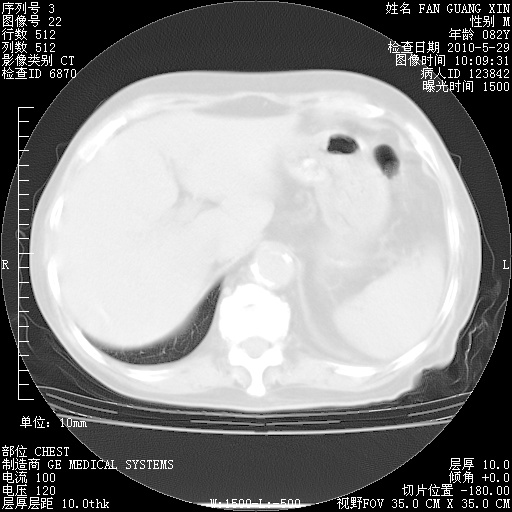

治疗3周后的肺部CT纵隔窗

再治疗10天后的肺部CT

再治疗10天后的肺部CT 纵膈窗